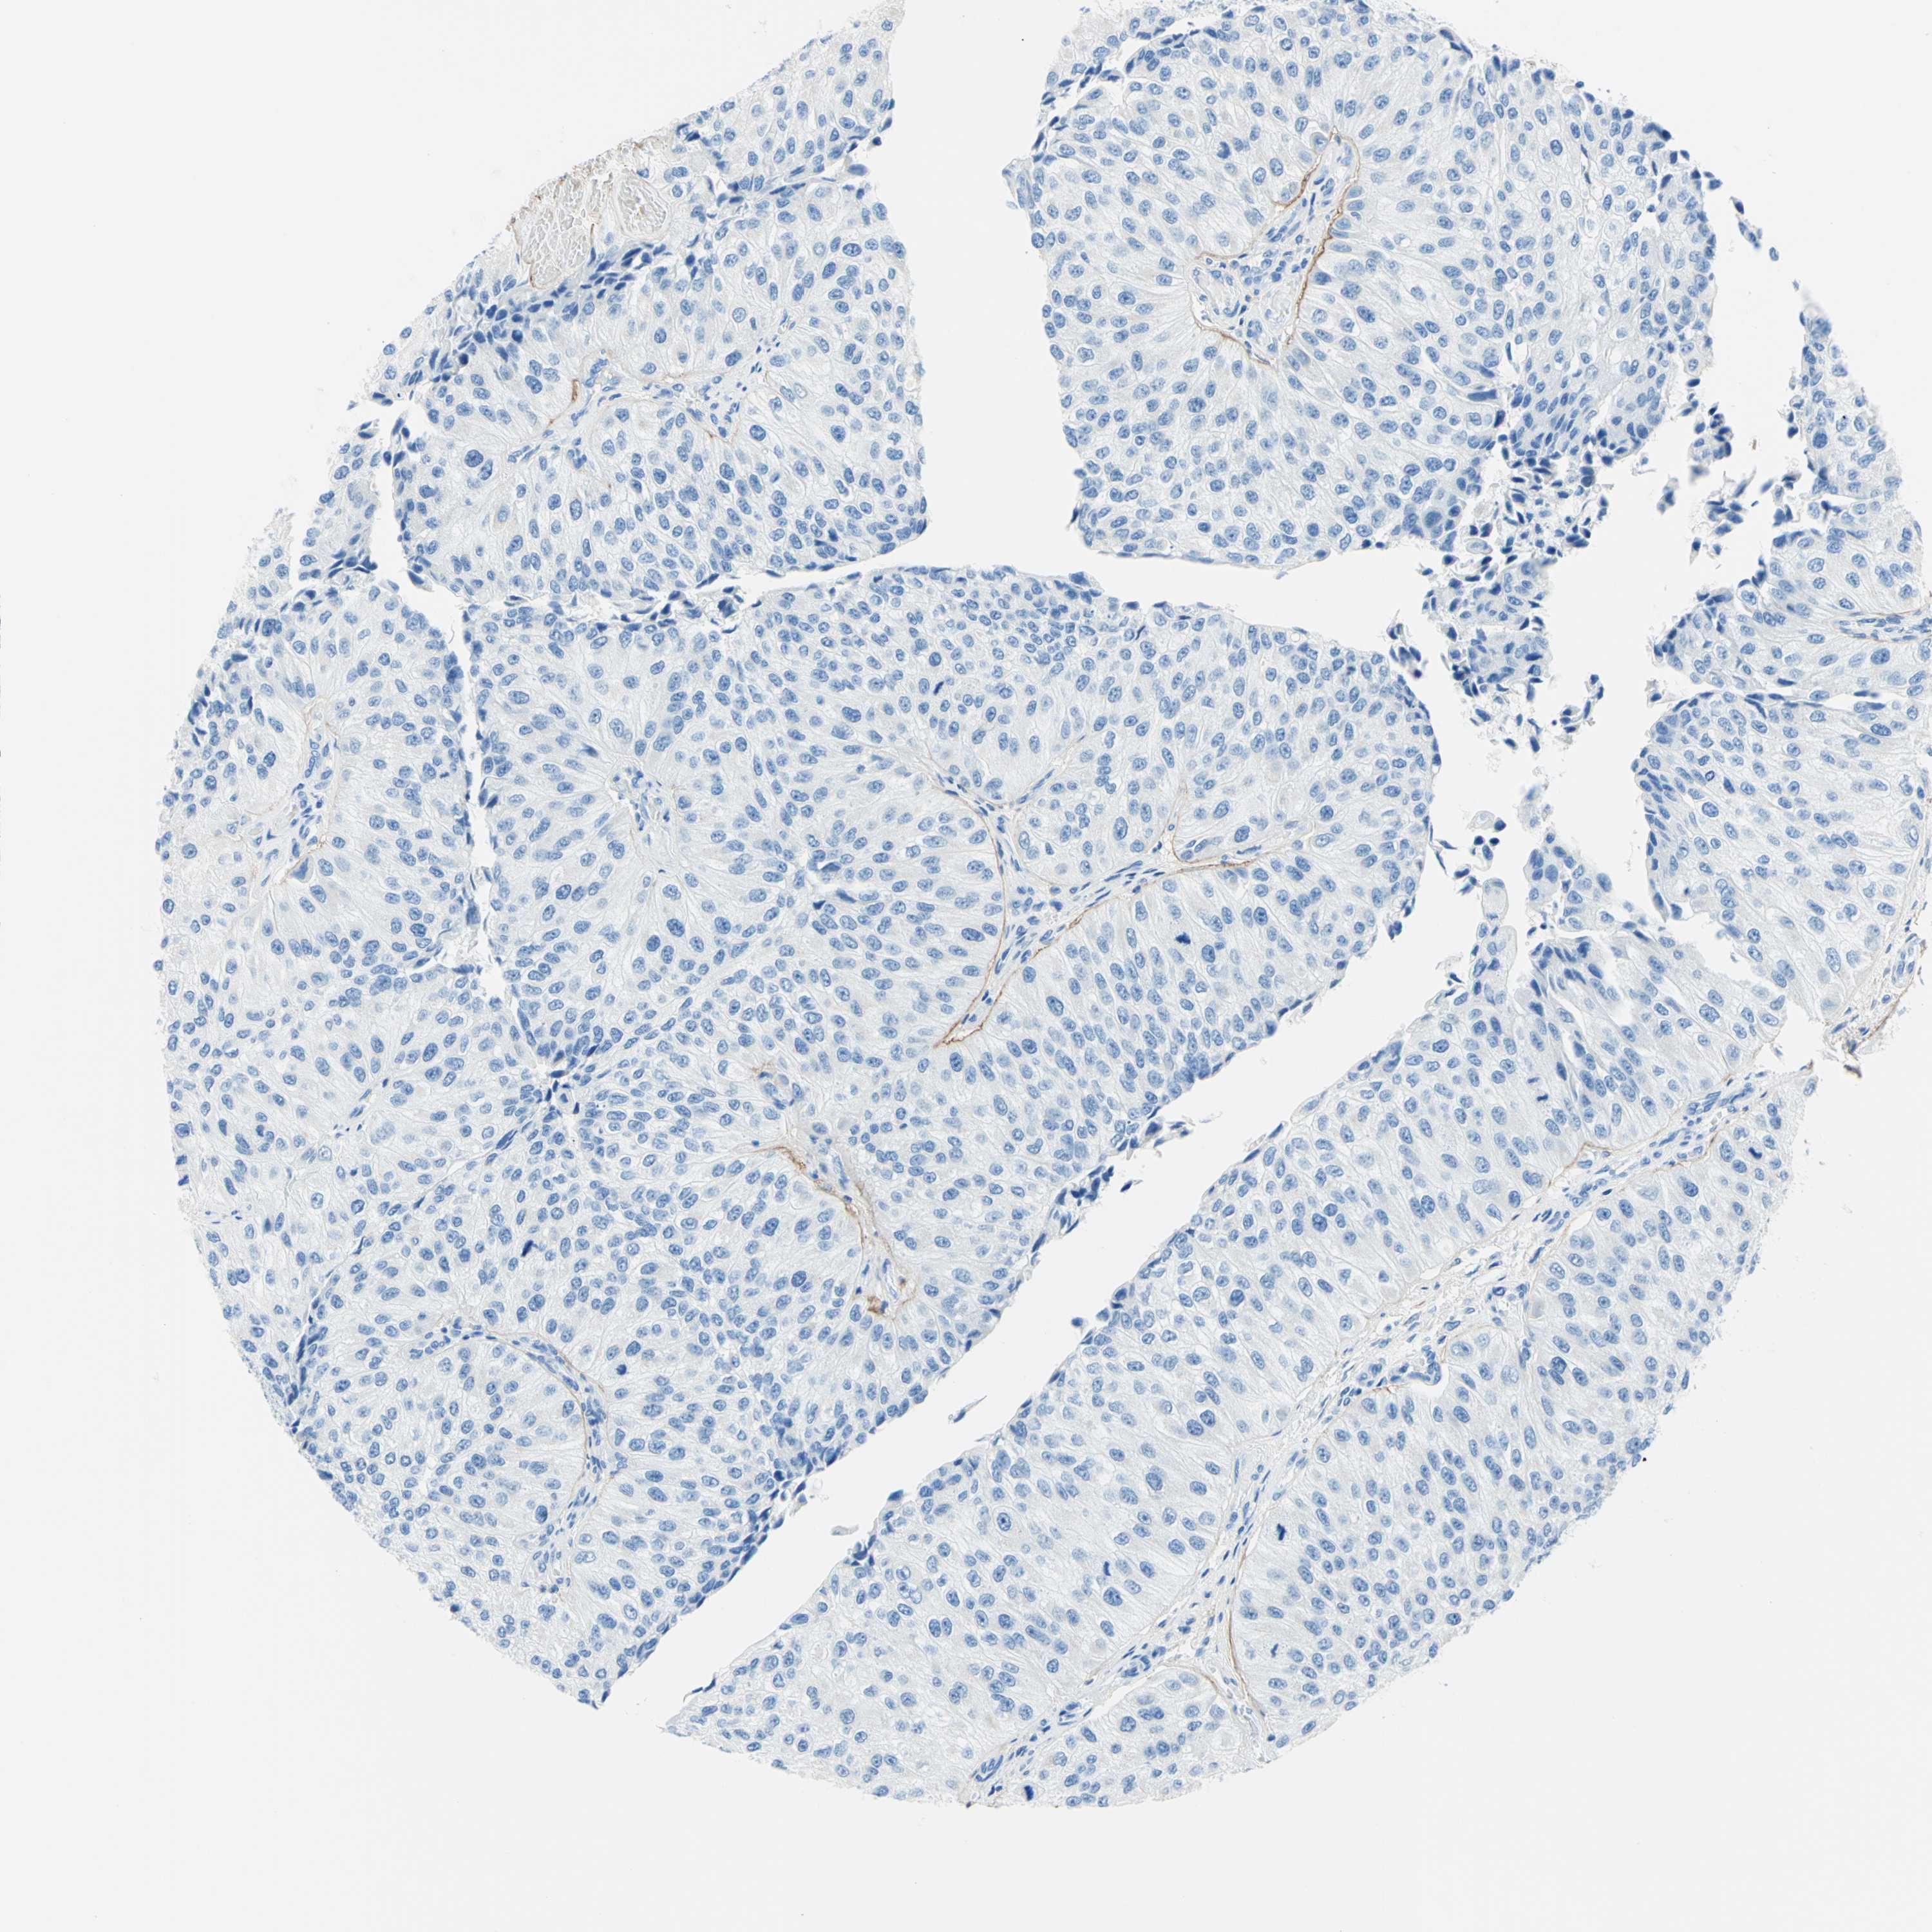

UROTHELIAL CANCER - Protein expressioni

A mouse-over function shows sample information and annotation data. Click on an image to view it in a full screen mode. Samples can be filtered based on level of antibody staining by selecting one or several of the following categories: high, medium, low and not detected. The assay and annotation is described here.

Note that samples used for immunohistochemistry by the Human Protein Atlas do not correspond to samples in the TCGA dataset.

Antibody stainingi

Antibody staining in the annotated cell types in the current human tissue is reported as not detected, low, medium, or high, based on conventional immunohistochemistry profiling in selected tissues. This score is based on the combination of the staining intensity and fraction of stained cells.

Each image is clickable and will lead to virtual microscopy that enables deeper exploration of all samples and also displays staining intensity scores, fraction scores and subcellular localization as well as patient and tissue information for each sample.

Antibody HPA010553

Staining

High

Medium

Low

Not detected

Intensity

Strong

Moderate

Weak

Negative

Quantity

>75%

75%-25%

<25%

None

Location

Nuclear

Cytoplasmic/membranous

Cytoplasmic/membranous,nuclear

Urothelial carcinoma, Low grade

Urothelial carcinoma, High grade